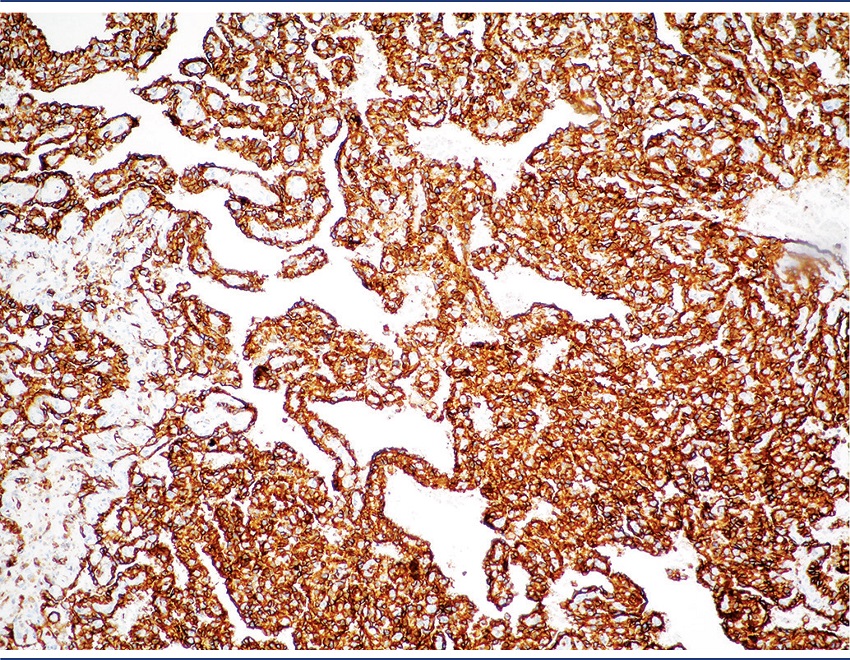

Immunohistochemistry reveals positivity for CD31 (90%) (Figure 8), CD34 (50%-74%) and friend leukemia integration 1 (FLI-1) (100%)(9). There can be positivity for cytokeratins in 35% of the cases, although most of them are of the epithelioid variant, uncommon in the heart(7,9).The most recent immunohistochemical markers with high sensitivity and specificity include nuclear factors ETS-related gene (ERG) and FLI-1(7). Values of Ki67 > 10% have been correlated with poor prognosis(9).